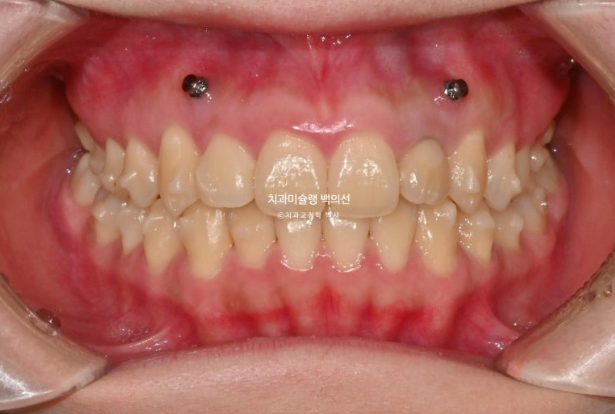

23.12~25.08

맞아진 중심선과 배열의 개선이 보입니다.

반대교합의 개선이 됩니다.

거미스마일과 잇몸돌출의 개선이 눈에 띕니다.